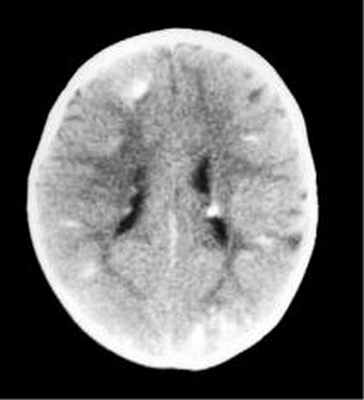

Субэпендимарные кальцификаты и корковые туберсы на КТ головного мозга ребенка с туберозным склерозом